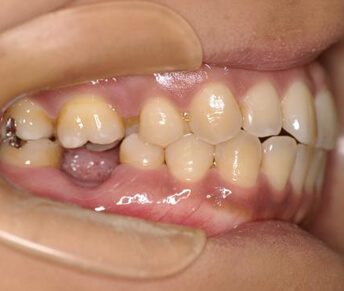

- 裏側からの矯正装置

(リンガルブラケット装置)

メリット

- ・装置が見えない。

デメリット

- ・構造的に装置と装置の間隔が狭い為ワイヤーの弾力を利用しにくいので歯を並べるのに時間がかかり、治療期間が長くなる。

- ・舌を動かしにくいので、正しい発音が出来ない。

- ・装置が舌に当たり舌に口内炎ができ易いので、食事に苦労する。

- ・歯みがきがしにくく、歯周病になりやすい。

- ・装置が裏側になるのでゴムやヘッドギアなどが使いにくいため、良い治療結果を得る事が難しい。

- ・裏側に装置があるので治療操作がし難く、毎回の治療時間が長く必要になる。

- ・装置自体が高価なのと、治療時間が長くかかるので治療費が高額になる。